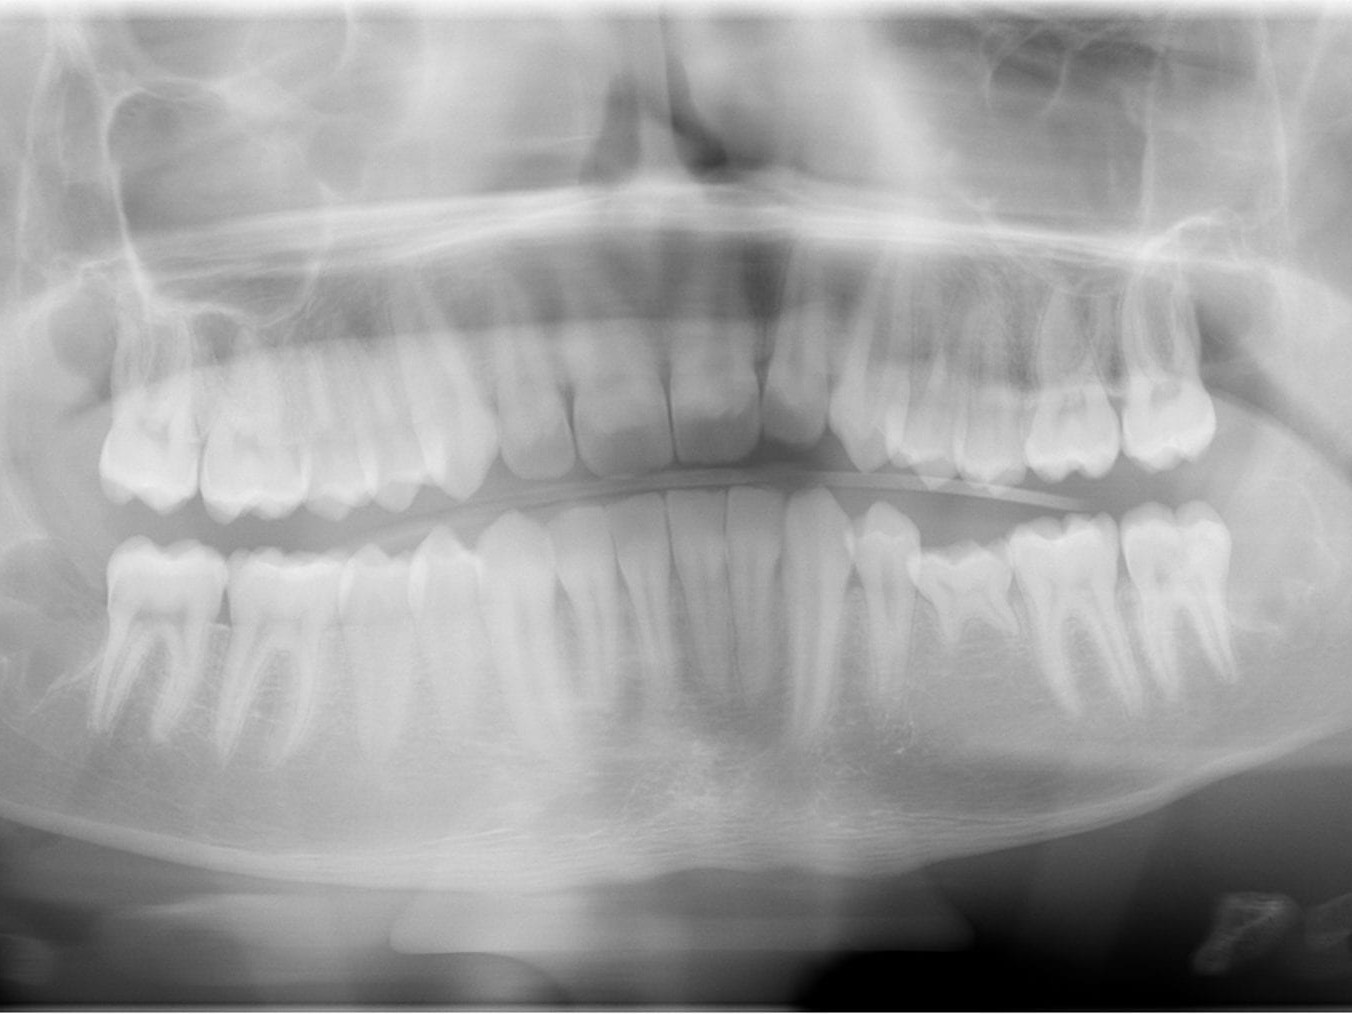

Im zweiten Fall war ein junger männlicher Patient mit persistierendem Milchzahn 75, der in Okklusion stand und keine Resorption seiner Wurzeln aufwies, zur Transplantation eines Weisheitszahns in diese Region überwiesen worden. Da diese klassische analoge Diagnostik bei retinierten Weisheitszähnen nicht möglich ist, wurde hier der digitale Weg mit DVT und Intraoralscan gewählt. So konnte im Vorfeld die Umsetzbarkeit dieses Überweisungsauftrags für den Patienten exakt berechnet werden (Abb. 3).

Die präoperative Planung umfasst klinische, radiologische und im Einzelfall modellbasierte Analysen von Transplantatlager und Transplantat. Voraussetzungen für eine erfolgreiche Therapie sind die Compliance des Patienten, der richtige Zeitpunkt, „Auswahl eines in Größe und Form geeigneten Transplantats, eine günstige okklusale Situation (Kieferrelation), ausreichende Platzverhältnisse des Transplantatlagers in allen Dimensionen sowie eine ausreichend breite attached Gingiva. […] Im Falle eines zu geringen mesial-distalen Platzangebots für das Transplantat kann eine initiale kieferorthopädische Therapie diskutiert werden.“ (13) Falls der Patient eine kieferorthopädische Vorbehandlung für inakzeptabel ansieht oder diese nicht Erfolg versprechend ist, besteht noch die Möglichkeit, die approximale Oberfläche des Transplantats bzw. der Nachbarzähne um bis zu 0,5 mm zu reduzieren. Hierbei muss sichergestellt werden, dass kein Dentin